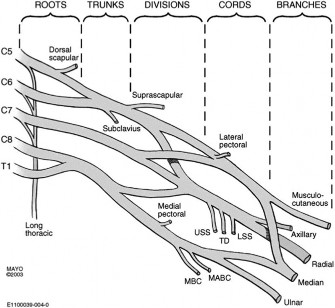

The correct answer is (C). This structure is a thickening of the coracohumeral ligament that starts anteriorly just posterior to the short head of the biceps tendon on the coracoid process, extends posteriorly through the edge of the avascular zone of the supraspinatus and infraspinatus, and ends at the inferior edge of the infraspinatus. One proposed function of the cable is to act like a cable in a suspension bridge, helping to evenly distribute forces on the humeral head produced by the rotator cuff (see Fig. 2–6).

Figure 2–6_Illustration showing the rotator cable and rotator crescent. B, rotator crescent; C, rotator cable; BT, biceps tendon; I, infraspinatus; S, supraspinatus; TM, teres minor. (Redrawn from Burkhart SS, Lo IKY. Arthroscopic rotator cuff repair. _J Am Acad Orthop Surg. 2006;14(6):333–346.)

The rotator crescent (Answer A) is the thin tissue that exists lateral to the rotator cable medial to the attachment of the supraspinatus and infraspinatus. It is composed on the tendons of these two rotator cuff muscles (see Fig. 2–6).

The rotator interval (Answer B) is the area on the anterior shoulder bordered by the subscapularis inferiorly and the supraspinatus superiorly.

The rotator cuff (Answer D) is composed of all four rotator cuff muscles, the supraspinatus, infraspinatus, teres minor, and subscapularis.